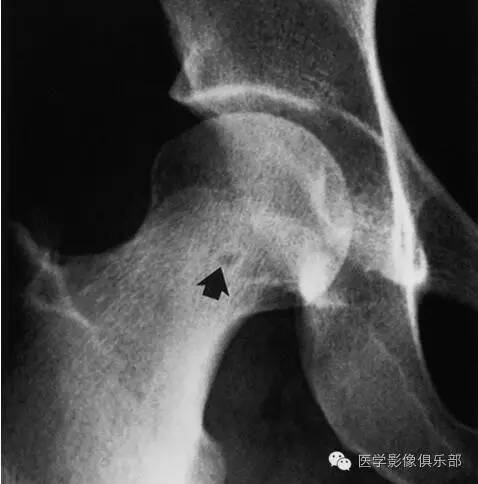

股骨颈疝窝

二者临床和影像学上表现相似,病理上也常很难区分,发病部位是主要的鉴别点。骨内腱鞘囊肿通常位于股骨头骨性关节面下方,局部关节面可伴增生硬化,相邻骨皮质少有裂隙。而股骨颈疝窝在病灶或相邻上下层面上大多可见与病灶相连的局限性裂隙样皮质缺损,不累及关节面。